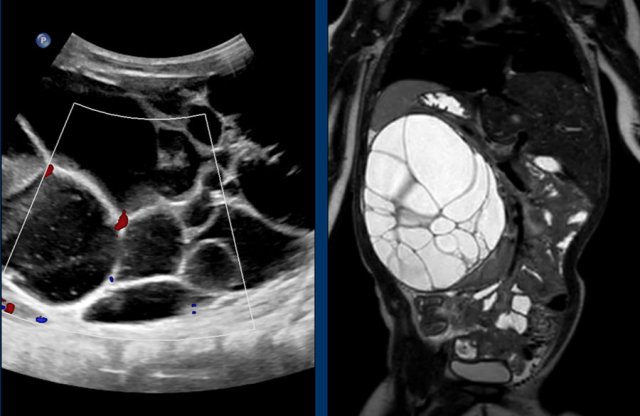

Multilocular cystic renal tumor

Cystic nephroma Cystic nephroma

Images

Ultrasound and MRI of a four-year-old boy with a multilocular cystic lesion in the interpolar region of the left kidney (arrow).

It was detected as an incidental finding at the age of nine months. On follow-up no change was seen. The lesion is consistent with a cystic nephroma, a benign condition.

The same lesion is seen on the T2 weighted transverse image.

These images are of a one-year-old girl.

On ultrasound a multicystic tumor was seen with some perfusion of septa.

T2 weigthed image better shows the extent of the lesion. A remnant of the normal renal tissue of the lower pole is visible, distinguishing it from a multicystic dysplastic kidney.

This tumor was diagnosed as a cystic nephroma for which right nephrectomy was performed.